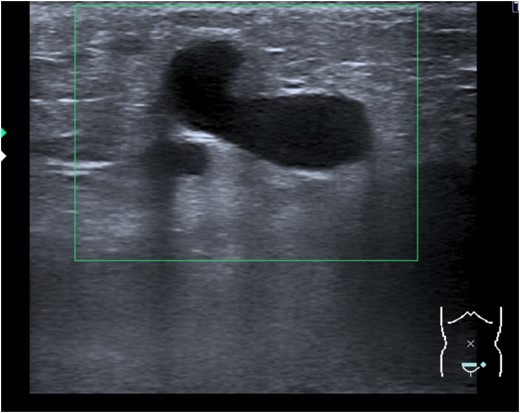

For verification of the clinical diagnosis a Doppler ultrasound was performed by an experienced ultrasound examiner. In the ultrasound a hernia with prolapsed intestine was diagnosed due to a tubular, hypoechoic, non-compressible, inguinal mass with no flow evident on color Doppler imaging (Fig. 2). However, it was unclear whether the hernia was caused by a bilateral or unilateral gap. Only for surgery planning purposes we decided to perform a CT scan to identify the side of the gap and classify the kind of hernia (direct/indirect). Surprisingly the CT scan showed large venous collaterals between left and right Vena femoralis and a illio-femoral thrombosis on the left side. No inguinal or any other hernia of the suprapubic and inguinal regions were found (Fig. 3). The venous collaterals showed extensive signs of inflammation—concordant with the diagnosis of a local suprapubic thrombophlebitis. After the CT scan the patient was re-evaluated by Doppler ultrasound. Knowing the CT scan results and by readjustment of Doppler settings that diagnosis was confirmed.

Tubular, hypoechoic, non-compressible, inguinal mass with no flow evident in color Doppler imaging.

Suprapubic crossover collaterals as clinical signs for a left iliac vein obstruction are an uncommon presentation in adults. The sonographic appearance mimicked a hernia by demonstrating a tubular, hypoechoic, non-compressible, inguinal mass with initially no flow evident on color Doppler imaging due to partial thrombosis of the venous collaterals. Further due to the thrombophlebitis of these aberrant vessels the patient presented with acute suprapubic pain and therefore the diagnosis of an acute inguinal hernia seemed to be obvious. However, the side of the hernia remained unsure und in order to better plan the operation a CT scan was performed with the reported unexpected result.